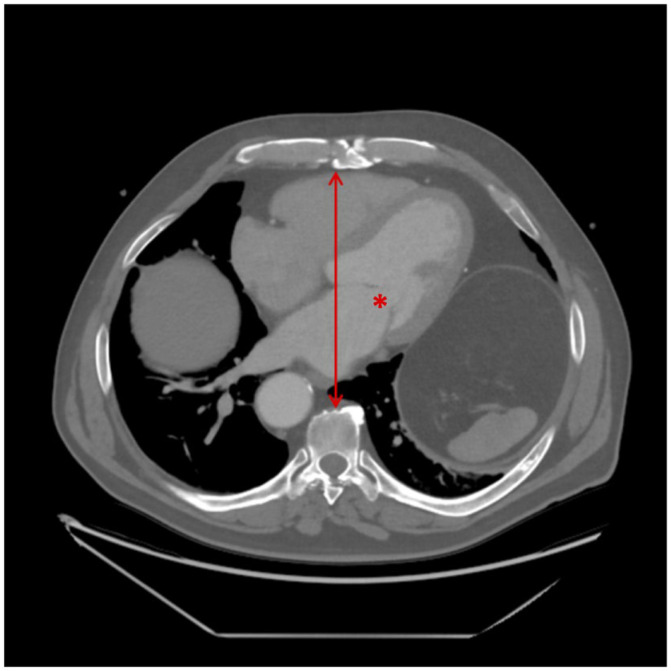

Background: Minimally invasive cardiac surgery (MICS) via right minithoracotomy is a safe, reproducible approach with excellent outcomes and reduced costs compared to median sternotomy. Despite careful patient selection, conversion to sternotomy occurs in 1-3% of cases and is associated with significantly higher morbidity and mortality. Small body habitus, particularly a short anteroposterior (AP) diameter, may increase the risk of conversion, but this has not been previously studied. This study aims to identify preoperative factors associated with conversion to improve patient selection for MICS. As cardiovascular surgery becomes increasingly personalized, identifying anatomical factors that predict technical complexity is essential. Methods: This retrospective study included 254 adult patients who underwent elective MICS between 2015 and 2024 at a tertiary hospital. Patient characteristics, computed tomography (CT) scans, intraoperative parameters, and postoperative outcomes were reviewed. AP diameter was defined as the distance from the posterior sternum to the anterior vertebral body at the mitral valve level on CT. Statistical analyses included Mann-Whitney and Fisher's exact/chi-square tests. Results: Conversion to sternotomy occurred in 1.6% of patients (n = 4). All converted patients were female. The converted group had a significantly shorter median AP diameter (100 mm vs. 124 mm, p = 0.020). Conversion was associated with higher rates of stroke and infection (25.0% vs. 0.8%, p = 0.047 for both), but no significant differences in hospital stay, bleeding, or renal failure. Conclusions: An AP diameter of less than 100 mm was associated with a higher risk of conversion to sternotomy in MICS. Incorporating simple, reproducible preoperative imaging metrics into surgical planning may advance precision-guided cardiac surgery and optimize patient outcomes.